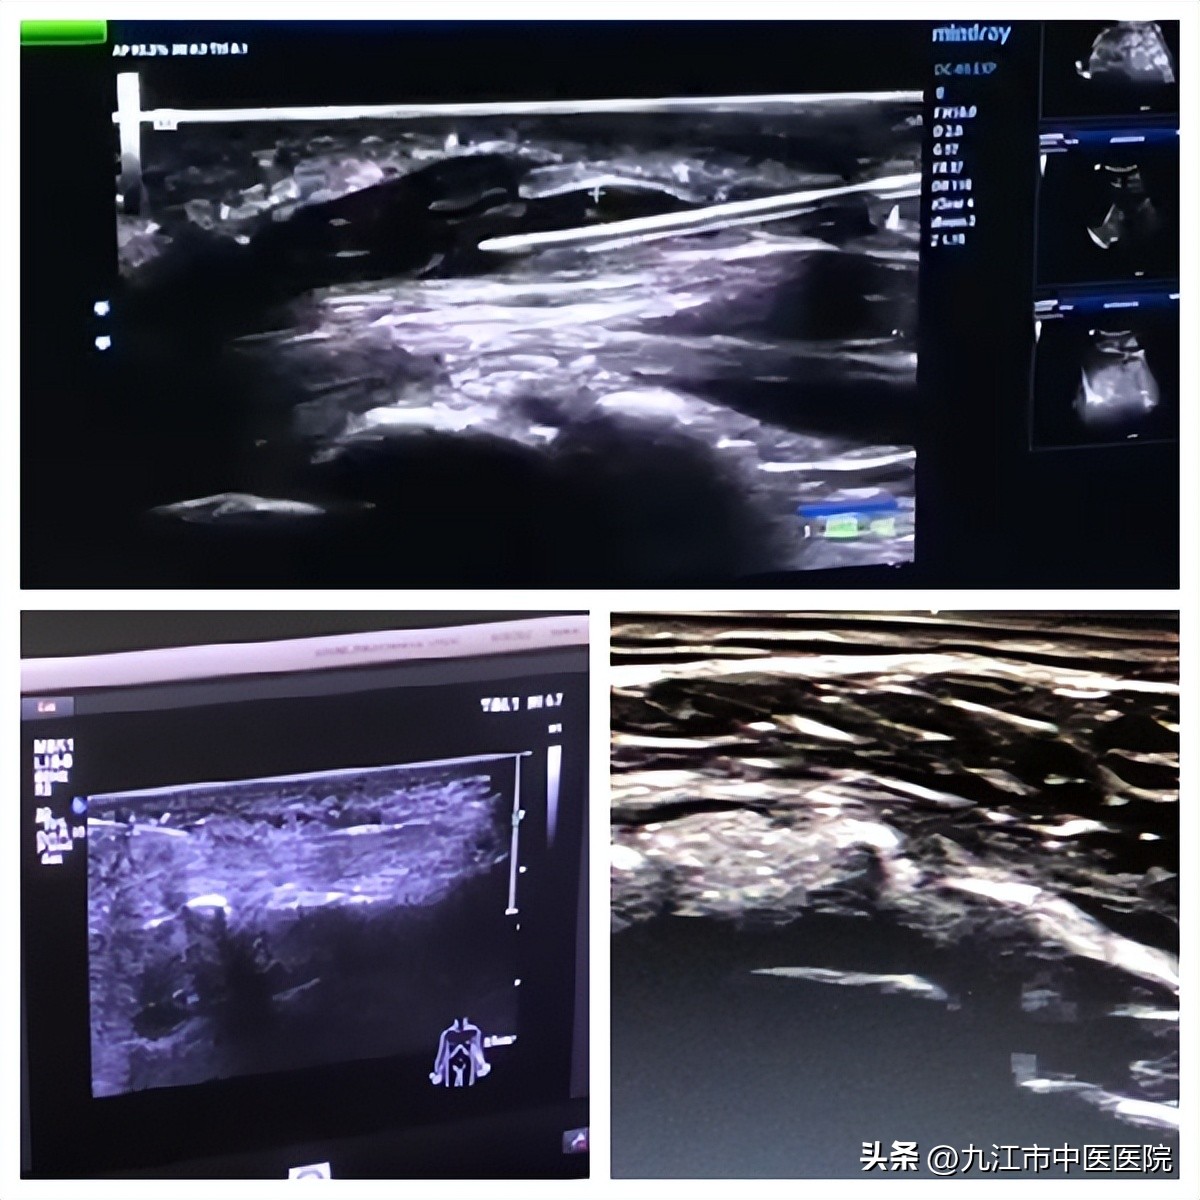

据了解,肌骨超声技术是近几年开展新兴技术,通过通过高频超声探头,可观察人体肌肉、肌腱、韧带、周围神经等组织结构及其发生的病变,从而对肌肉、骨骼、神经等方面的疾病进行精准诊断,并进行超声介入穿刺治疗。

肌骨超声和中西医临床的融合与发展,是中医药事业守正创新的一项工作亮点。其可视化治疗大大降低了术中操作风险,对患者操作创伤小、操作简便,治疗价格较低、贴合患者需求,这一新技术的应用,使得肌骨及周围神经疾病的诊断更加准确、清晰,可以满足诸多骨肌及周围神经疾病患者的就诊需求,辅助临床精准了解病因,解除患者病痛。

超声下抽吸钙化性肌腱内钙化病灶、松解指屈腱鞘炎、松解腕管综合征

在科室负责人、骨伤二科副主任余学文的带领下,骨伤二科目前已成功开展多例肌骨超声结合传统中医治疗各类常见骨科疾病,如黏连性肩关节囊炎、钙化性肌腱炎,肱骨外上髁炎、腕管综合征、指屈腱鞘炎、梨状肌综合征、坐骨神经痛、膝关节炎、足底筋膜炎等疾病的诊断及治疗操作。